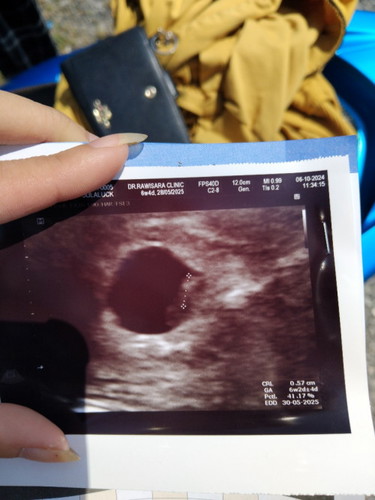

เจอจิ๋วๆแล้วค่ะแม่ๆ ประจำเดือนล่าสุด22 สิงหาคม

นับตามประจำเดือน 6+4 แต่หมอวัดได้ตามขนาดเด็กจิ๋วได้6+2 เคยท้องนอกมดลูกมา ตอนนี้น้องอยู่ในมดลูกแล้วค่ะ ฮีลใจขึ้นเยอะเลย